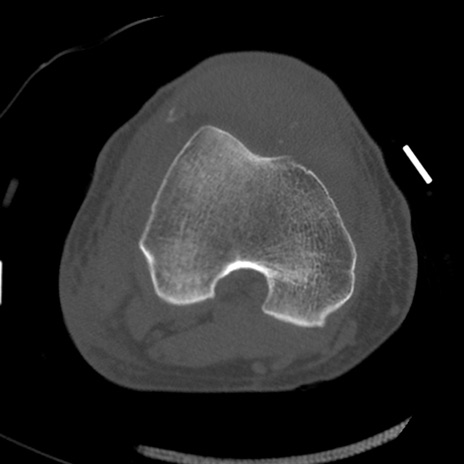

症例28 右膝関節CT(横断像)

右膝関節CT